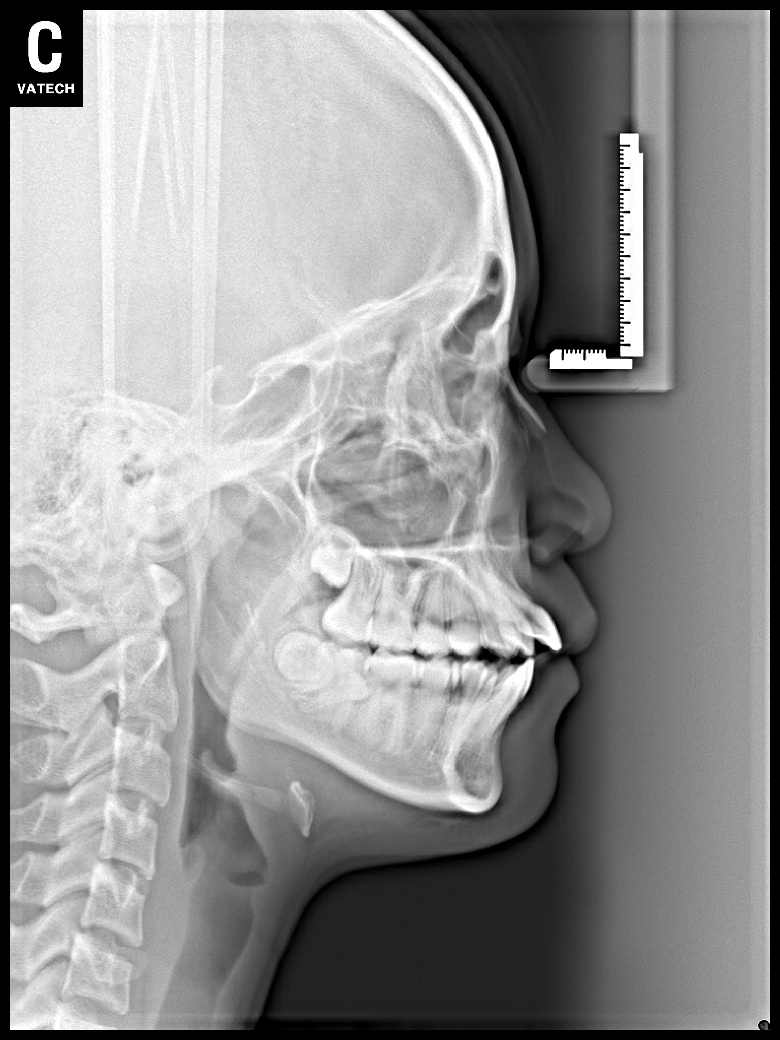

치료 후 사진입니다.